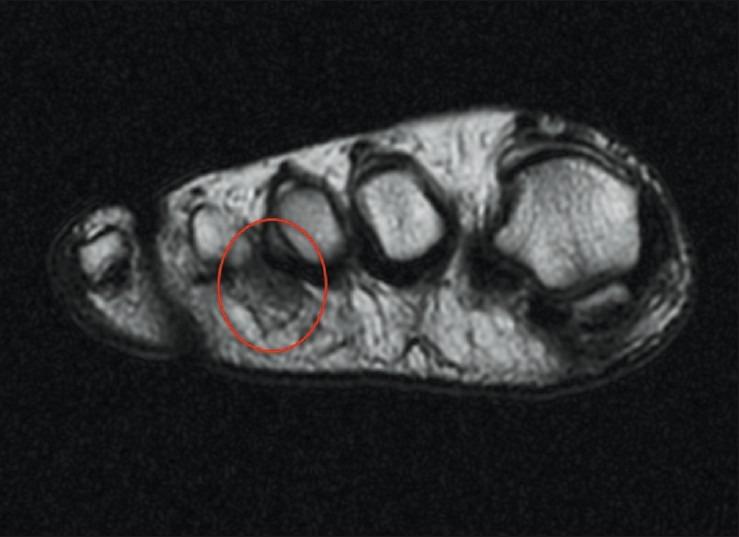

The diagnosis of Morton's neuroma is based primarily on clinical findings. Ultrasonography (US) and magnetic resonance image (MRI) studies are considered complementary diagnostic techniques. The aim of this study was to establish the correlation and sensitivity of both techniques used to diagnose Morton's neuroma.

Thirty seven patients (43 intermetatarsal spaces) with Morton's neuroma operated were retrospectively reviewed. In all cases MRI or ultrasound was performed to complement clinical diagnosis of Morton's neuroma. In all cases, a histopathological examination confirmed the diagnosis. Estimates of sensitivity were made and correlation (kappa statistics) was assessed for both techniques.

Twenty seven women and 10 men participated with a mean age of 60 years. Double lesions presented in six patients. The second intermetatarsal space was affected in 10 patients and the third in 33 patients. An MRI was performed in 41 cases and a US in 23 cases. In 21 patients, both an MRI and a US were performed. With regard to the 41 MRIs performed, 34 were positive for Morton's neuroma and 7 were negative. MRI sensitivity was 82.9% [95% confidence interval (CI): 0.679-0.929]. Thirteen out of 23 US performed were positive and 10 US were negative. US sensitivity was 56.5% (95% CI: 0.345-0.768). Relative to the 21 patients on whom both techniques were carried out, the agreement between both techniques was poor (kappa statistics 0.31).

Although ancillary studies may be required to confirm the clinical diagnosis in some cases, they are probably not necessary for the diagnosis of Morton's neuroma. MRI had a higher sensitivity than US and should be considered the technique of choice in those cases. However, a negative result does not exclude the diagnosis (false negative 17%).